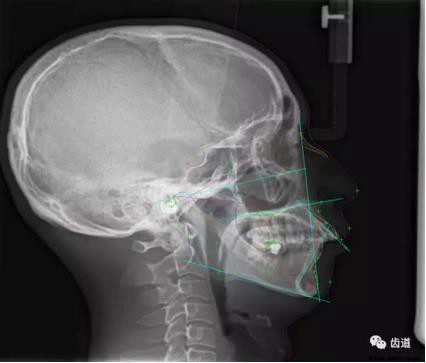

五)口腔正畸

CBCT在頜骨正畸科方面的應(yīng)用:軟件功能的強大,提供有效的數(shù)據(jù),為頜骨正畸提供了極大的幫助,免除了很多臨床醫(yī)生的手工繪圖,并有利于科研、教學(xué)等方面發(fā)展研究。

投影測量側(cè)位片影像

軟件產(chǎn)生CEPH圖像注釋,不含X線射線圖像